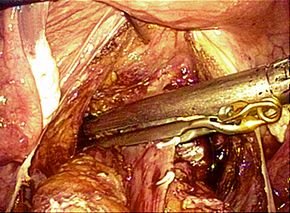

腹腔鏡手術で胆嚢の摘出と総胆管結石の摘除を同時に行います。胆嚢摘出後、十二指腸

上部総胆管を切開し、胆道鏡を用いて直視下に胆石を除去します。

採石後は胆道鏡で結石遺残のないことを確認します。その後胆管切開部を腹腔鏡下に

体内で結紮縫合を行い、閉鎖します。